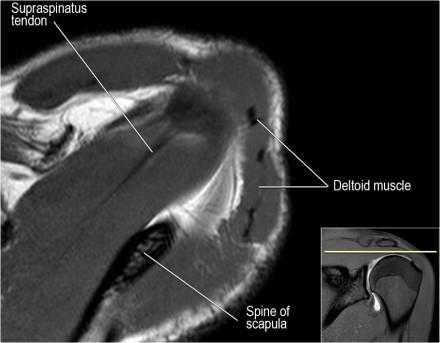

Нормальная сагиттальная анатомия и контрольный список

- обратите внимание на мышцы манжеты вращателей и поищите их атрофию

- обратите внимание на среднюю плече-лопаточную связку, которая имеет косое направление в полости сустава, и изучите отношение к сухожилию подлопаточной мышцы

- на данном уровне иногда видны повреждения суставной губы в направлении на 3-6 часов

- изучите место прикрепления длинной головки двуглавой мышцы плеча к суставной губе (biceps anchor)

- обратите внимание на форму акромиона

- поищите импинджмент за счет акромиально ключичного сустава. Обратите внимание на интервал между мажетой вращателей и клювовидно-плечевой связкой (coracohumeral ligament).

- поищите повреждение подостной мышцы